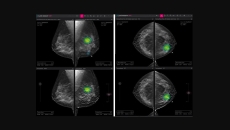

Also, Remidio receives a CE mark for its AI tool for detecting referable diabetic retinopathy.